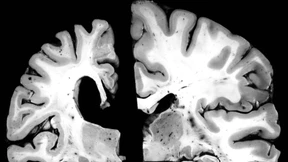

Wenn Ärzte verschiedene Stadien der Alzheimer-Demenz unterscheiden können, können sie die Gabe neuer Medikamente individuell optimieren. Ein neuer Biomarker soll Patienten unnötige Therapien ersparen.